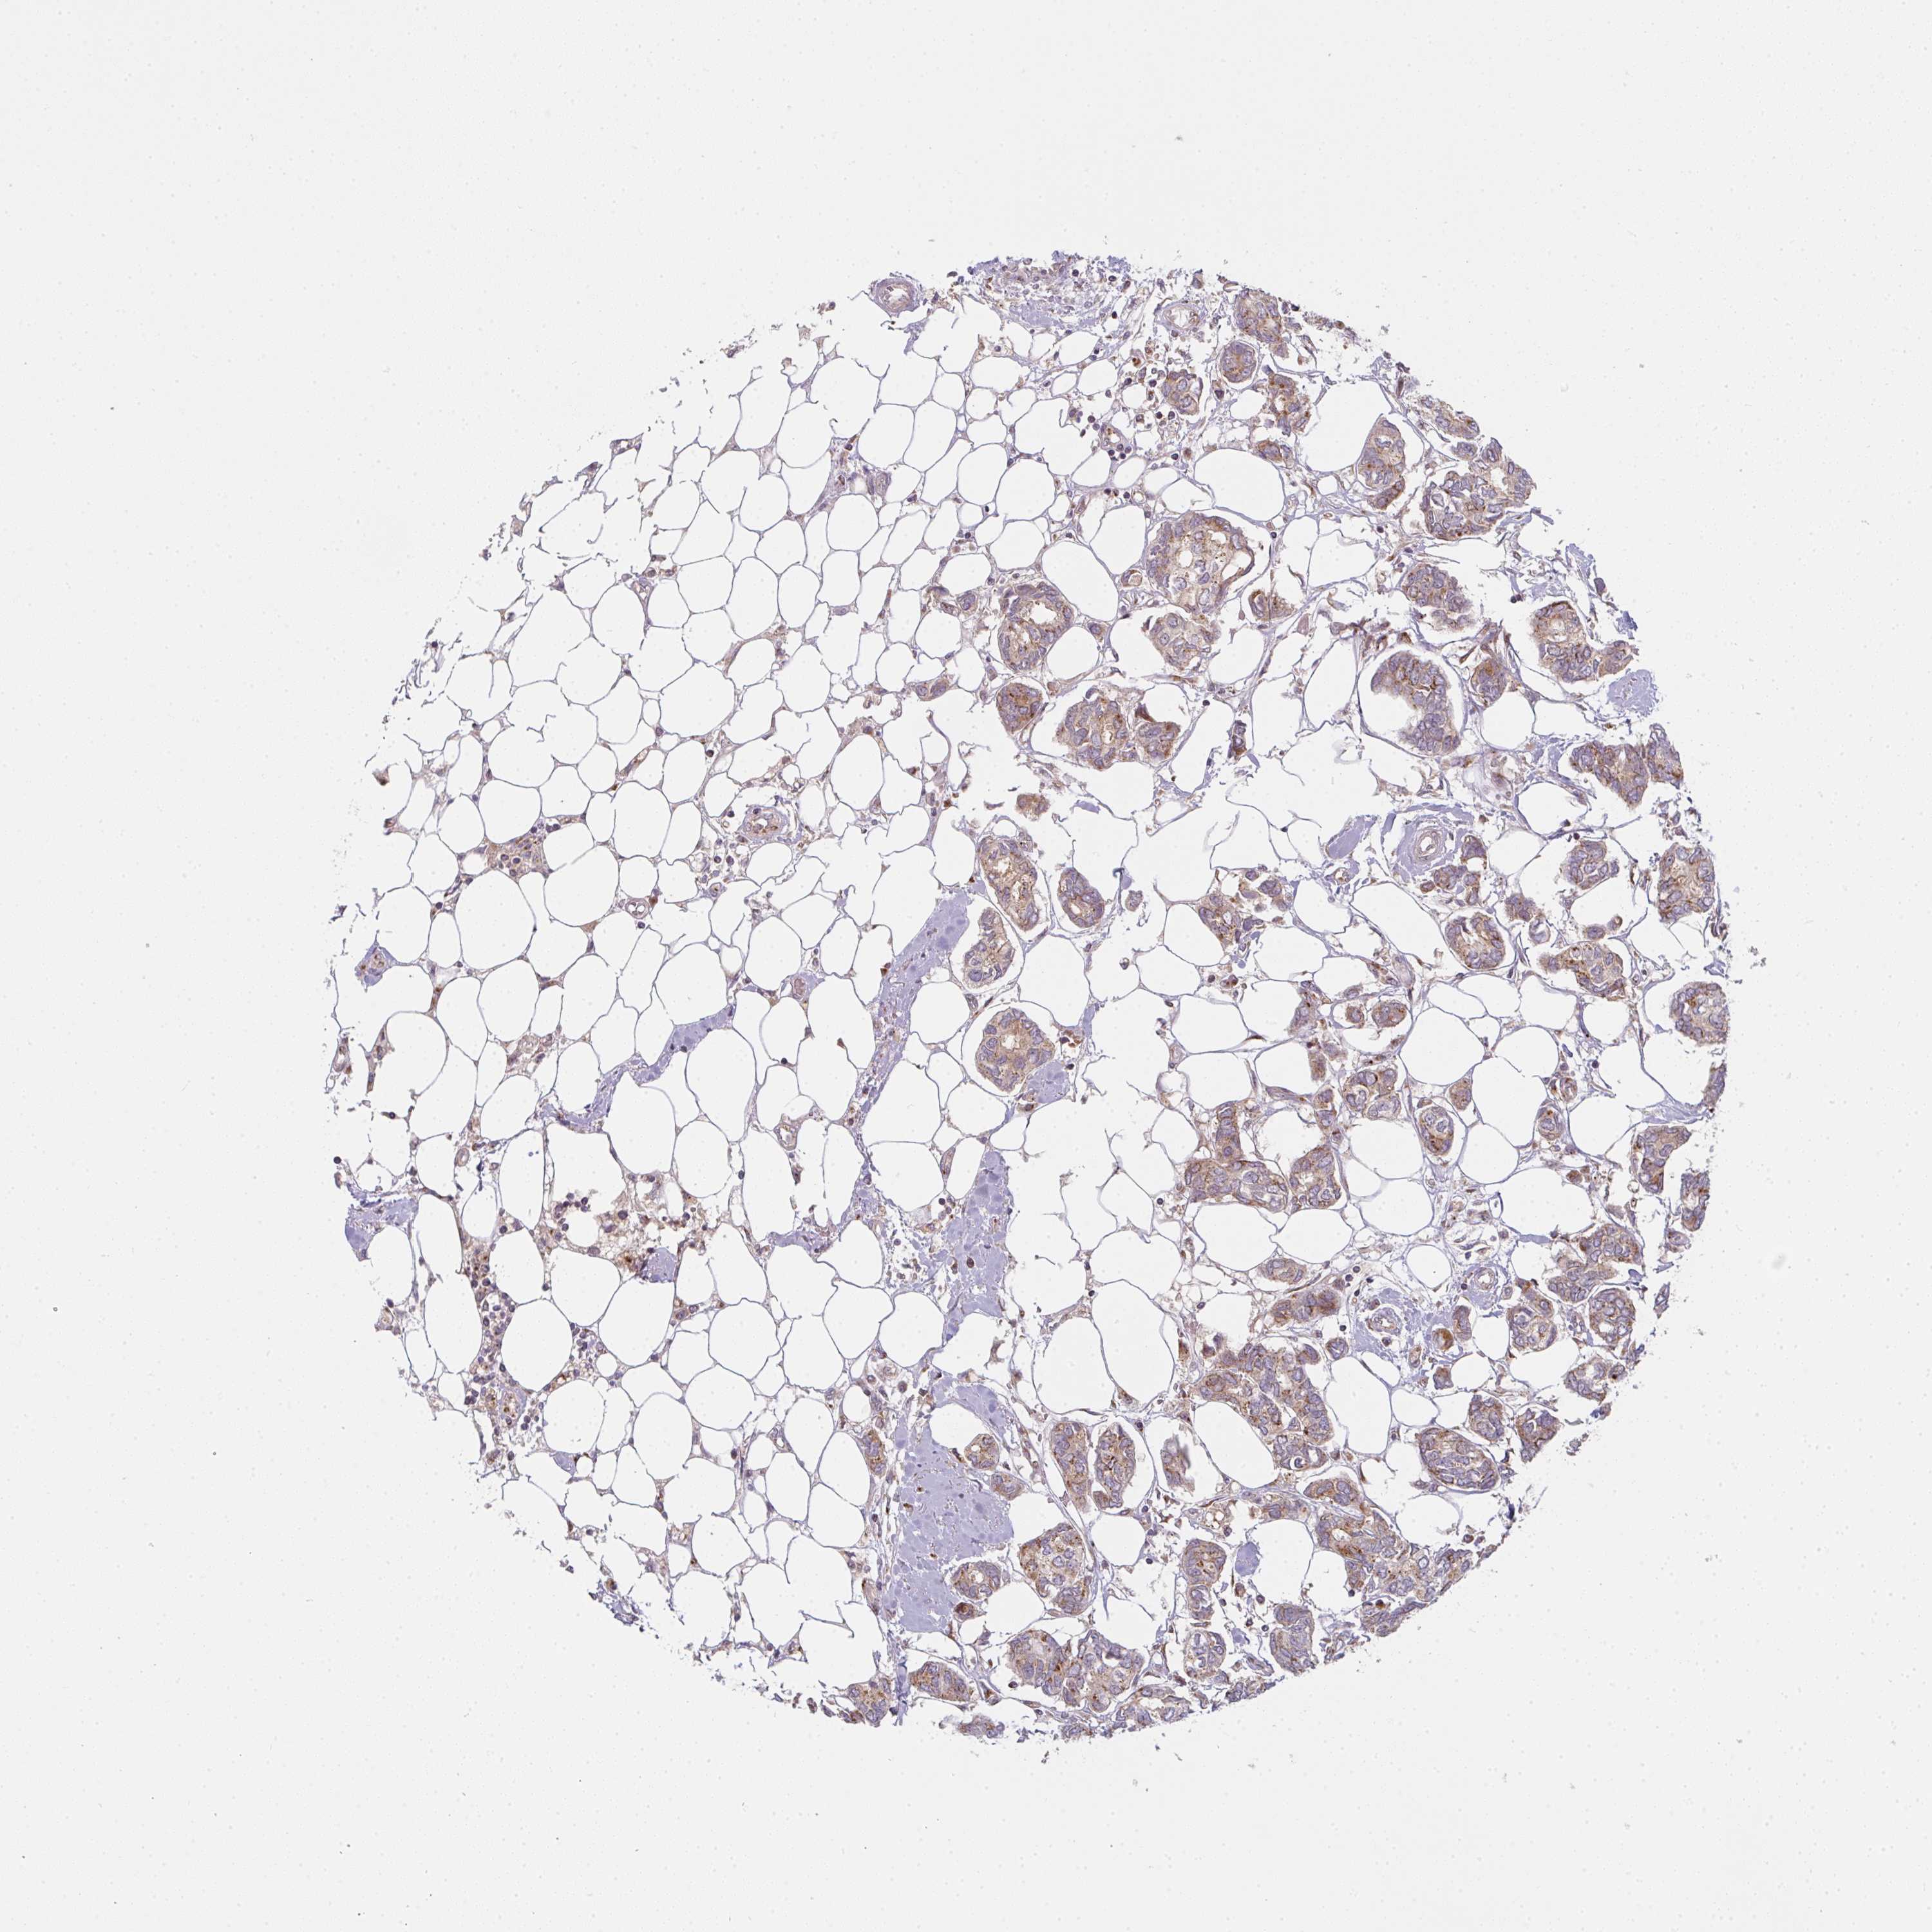

CANCER BREAST CANCER Show tissue menu

BRCA TCGA BRCA VALIDATION PROTEIN EXPRESSION